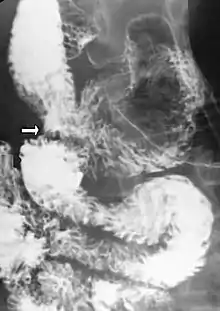

Diagnosis is very difficult, and usually one of exclusion. SMA syndrome is thus considered only after patients have undergone an extensive evaluation of their gastrointestinal tract including upper endoscopy, and evaluation for various malabsorptive, ulcerative and inflammatory intestinal conditions with a higher diagnostic frequency. Diagnosis may follow X-ray examination revealing duodenal dilation followed by abrupt constriction proximal to the overlying SMA, as well as a delay in transit of four to six hours through the gastroduodenal region. Standard diagnostic exams include abdominal and pelvic computed tomography (CT) scan with oral and IV contrast, upper gastrointestinal series (UGI), and, for equivocal cases, hypotonic duodenography. In addition, vascular imaging studies such as ultrasound and contrast angiography may be used to indicate increased bloodflow velocity through the SMA or a narrowed SMA angle.[12][13]

Upper gastrointestinal series showing extreme duodenal dilation (white arrow) abruptly preceding constriction by the SMA.